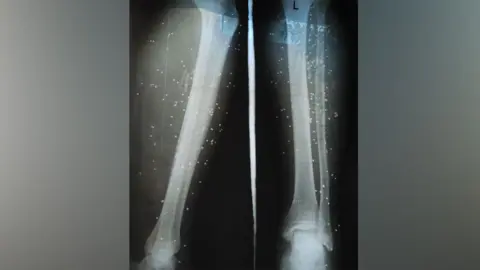

Devendra, a farmer, recounts the moment he was bitten while picking mulberry leaves, stating, I went to the hospital four days after I was bitten, when the pain became unbearable. But the delay cost me my leg. His story is a heartbreaking metaphor for the struggle many face in regions heavily burdened by snakebite incidents.

A report by the Global Snakebite Taskforce revealed that 99% of healthcare workers in India encounter obstacles when administering life-saving antivenom. The survey of 904 professionals revealed systemic issues: poor infrastructure, lack of antivenom access, and inadequate training. Nearly half reported that delays in treatment led to serious complications, such as amputations and lifelong mobility problems.